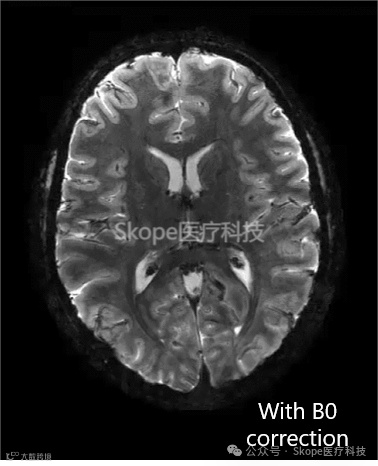

校正静态B0场不均匀性

Skope的场摄像头捕获编码场的动态变化。通过基于多回波梯度回波扫描生成的B0场图,skope-i考虑了静态场的不均匀性。B0场校正可减少依赖于所使用的编码方案的位移或模糊。

*30个螺旋交错,读出长度为20毫秒(来源:Skope)

Courtesy IBT, ETH Zurich and University of Zurich